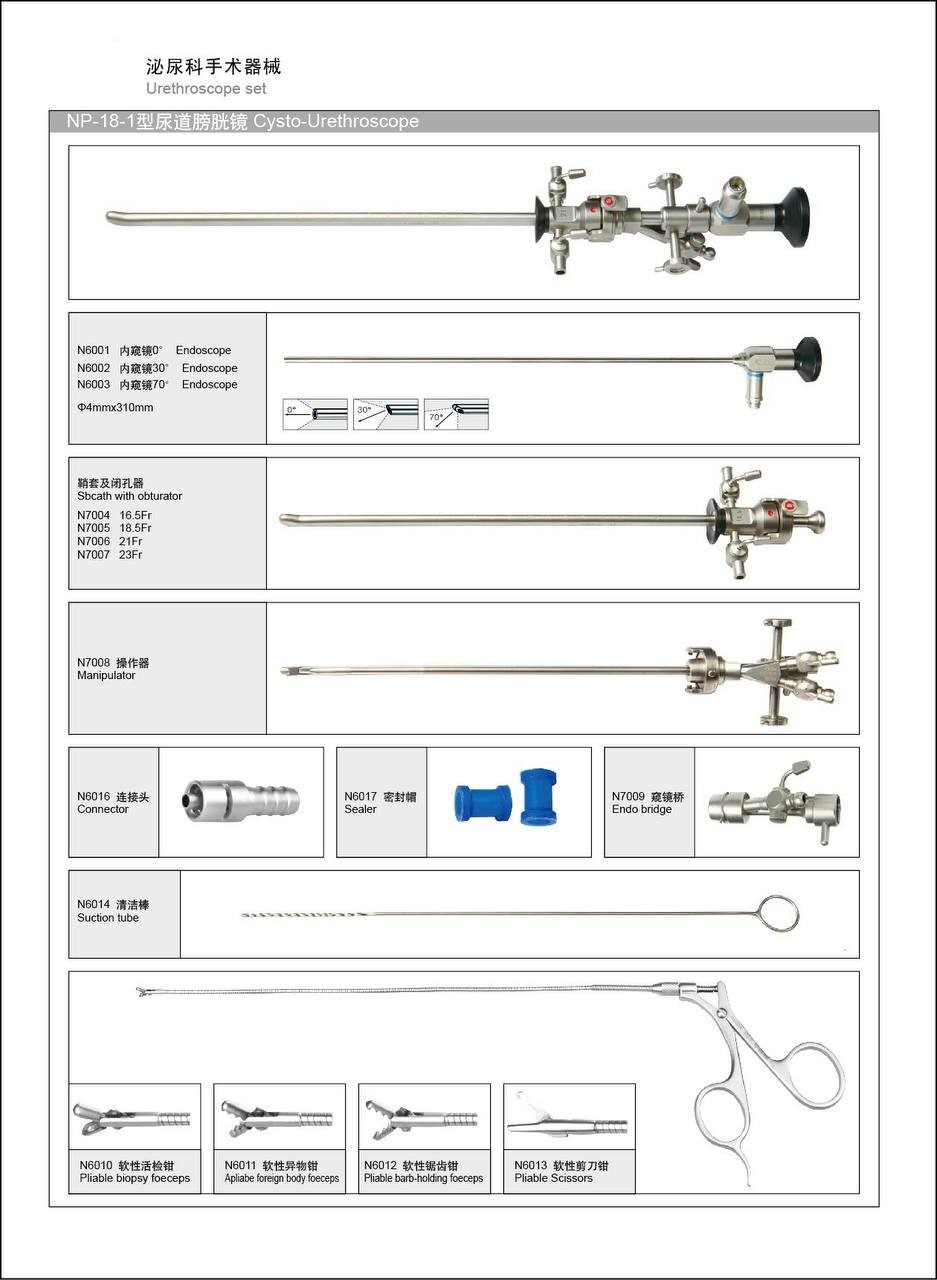

泌尿手术器械

项目类型

体验医疗区2

起投金额

1000USDT

每日释放:0.83

释放周期:9 天

已购: 21000

剩余: 0